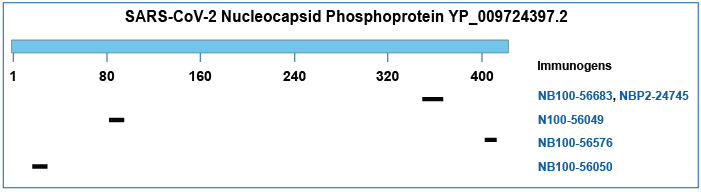

用于检测 SARS-CoV 核衣壳蛋白的抗体:

最近美国国立卫生研究院的一项研究成功建立了 SARS-CoV-2 感染的恒河猴动物模型,并利用兔多克隆抗 SARS-CoV 核衣壳抗体(货号 NB100-56576)成功检测了 SARS-CoV-2 病毒在感染组织中的存在。